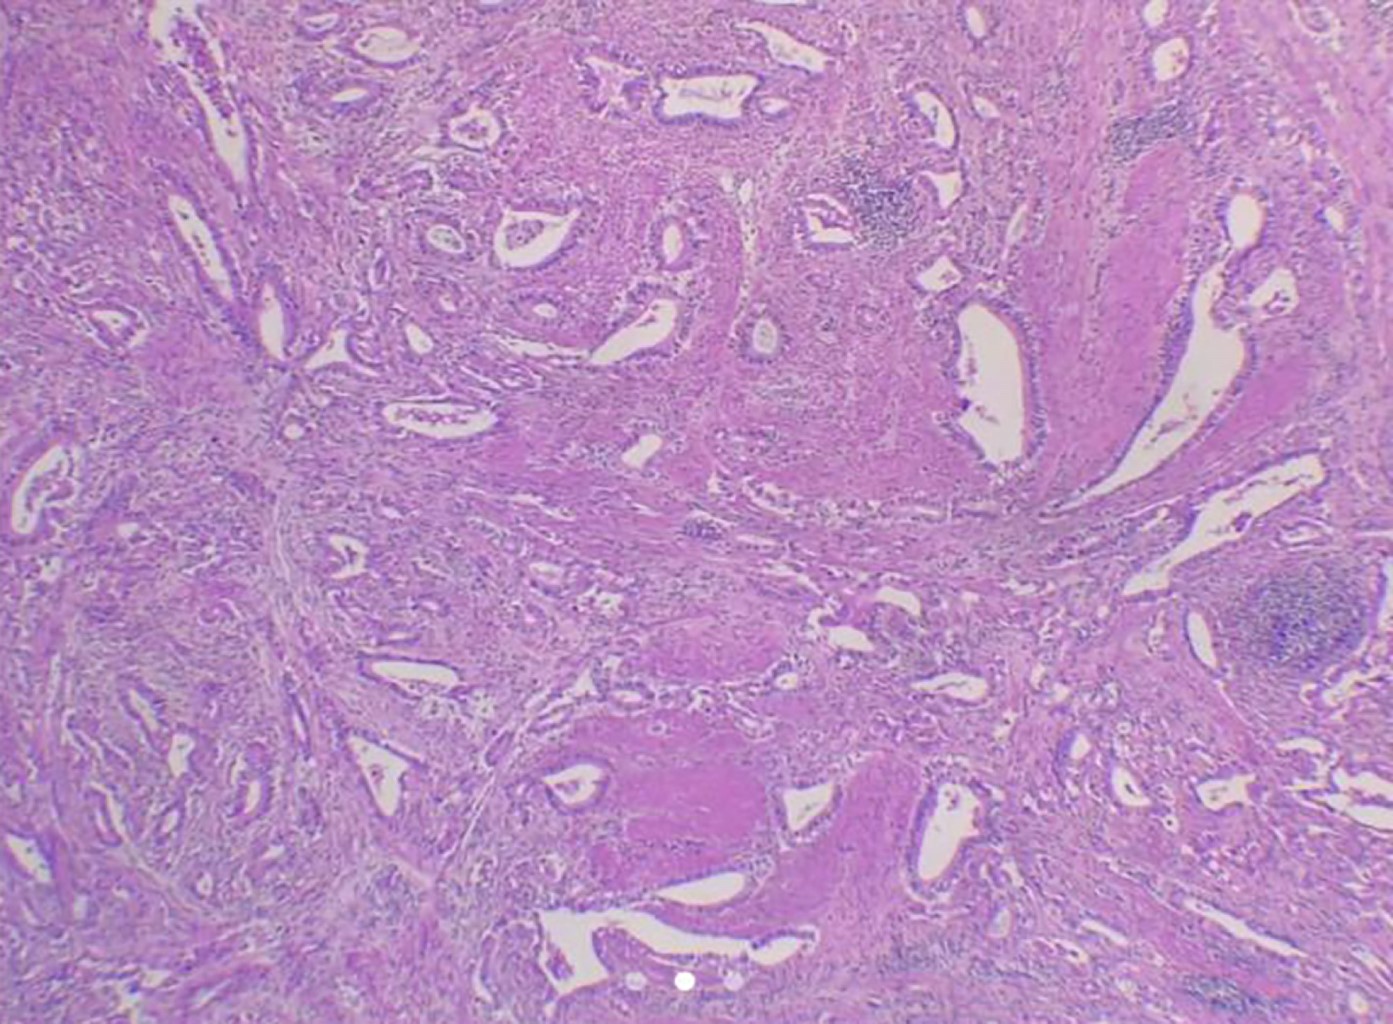

Recurrent gastric adenocarcinoma with metastasis to the rectum

Introduction: the most common sites of gastric adenocarcinoma metastases are the liver, peritoneum, and lungs, with reports in the colon and rectum being rare. Clinical case: we describe a patient in remission of an intestinal gastric adenocarcinoma with resection and chemoradiation about three years before presenting a rectal recurrence with uterine involvement compatible with metastatic gastric adenocarcinoma. Conclusion: the latency theory is proposed as a possible cause of metastasis, especially in patients with a history of cancer, due to the time elapsed between the initial appearance and the final metastasis to the rectum.

Figure 1

Figure 2

Figure 3